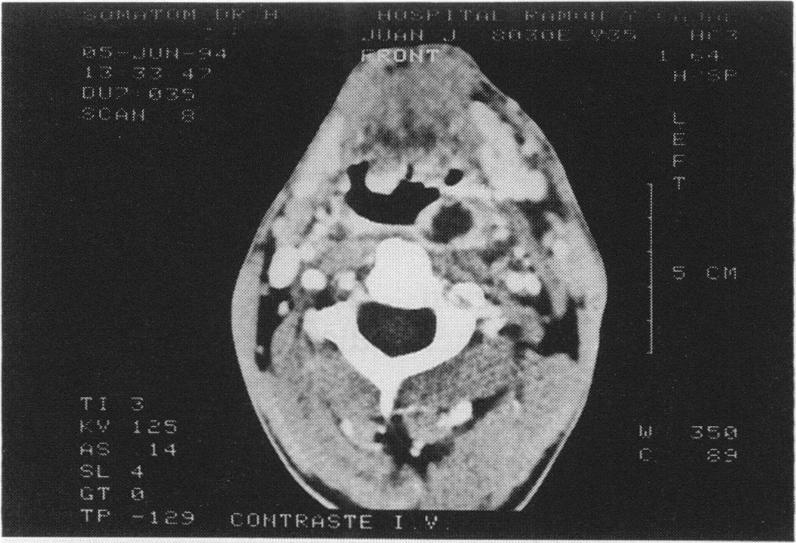

Acute confusion in a young man.